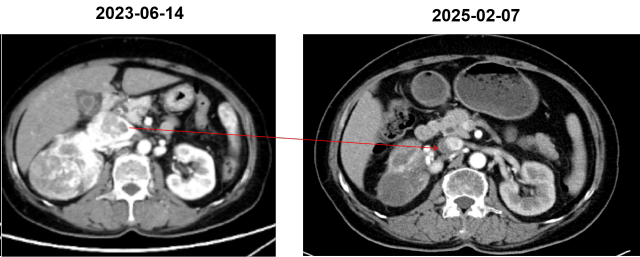

<p><strong>摘要</strong></p><p>女性，64 岁<br/>主诉：血尿1周，检查发现右肾肿瘤，于 2023-06-17 就诊于我科<br/>查体：浅表淋巴结未触及肿大，心、肺、腹（-）<br/>ECOG 评分：1 分<br/>既往史：子宫肌瘤术后 20 年；神经衰弱病史 1 年，佐匹克隆治疗；高血压病史 20 年，硝苯地平、利血平治疗。</p><p><strong><br/></strong></p><p><strong>临床资料</strong></p><p>一、辅助检查</p><p>肾脏 MR 平扫＋动态增强：右肾中上份为主见类椭圆形等 T1 等 T2 信号肿物，截面约 8.0×6.5cm，T1WI 反相位部分区域信号强度减低，DWI 及 ADC 扩散受限，呈不均匀快进快出强化模式；病灶侵及部分右肾静脉-下腔静脉，以上水平下腔静脉全程粗大，可见团状不均匀强化充盈缺损，肝中静脉内见条状充盈缺损区，符合右肾恶性肿瘤（CCRCC 可能大）累及部分右肾静脉并下腔静脉瘤栓，肝中静脉栓子形成 MR 表现。</p><p>病理：2023-06-19 行右肾穿刺活检术：（右肾占位穿刺）符合透明细胞性肾细胞癌。 免疫组化：CA9（+），Vimentin（+），CK7（-），TFE3（-），FH（+），PAX8（+），CD117（-）。</p><p>2023-06-14 泌尿系 CTU 增强：右肾及下腔静脉内富血供肿块，右肾癌并腔静脉癌栓达膈肌以上，肾占位最大横截面 9.9*6.1cm，腔静脉占位最大横截面 6.1cm，上下范围 12.4cm，可见肝静脉栓子。</p><p style="text-align: center;"><img src="https://img1.dxycdn.com/p/s10/2025/1124/477/6332268857029482991.png!w640" alt="图片1.png"/></p><p>二、诊断与鉴别诊断</p><p>初步诊断：右肾透明细胞癌并腔静脉瘤栓；肝静脉癌栓</p><p>分期：cT3bN0M0</p><p><br/></p><p><strong>治疗情况</strong></p><p>2024-09-13 ： 胸部+全腹部(含盆腔）CT 平扫+增强 ：右肾中上份见一类椭圆形略低密度灶，较大截面约 5.5×4.0cm，边界欠清，增强扫描呈欠均匀轻度强化，较前增大，病灶侵及部分右肾静脉-下腔静脉，以上水平下腔静脉全程粗大，较宽处约 3.8cm。右肾恶性肿瘤并右肾静脉、下腔静脉治疗后 CT 所见。</p><p>2024-11-01： 胸部+全腹部(含盆腔）CT 平扫+增强 ：右肾中上份见一类椭圆形略低密度灶，较大截面约 5.5×4.0cm，边界欠清，增强扫描呈欠均匀轻度强化，较前变化不明显，病灶侵及部分右肾静脉-下腔静脉，以上水平下腔静脉全程粗大，较宽处约 3.8cm 右肾恶性肿瘤并右肾静脉、下腔静脉治疗后CT所见，较前变化不明显 SD。<br/>胃肠道反应较重，恶心纳差乏力伴声音嘶哑反应较重，高血压，AE3 级。</p><p>2024-11-01：再次换用舒尼替尼 50mg，2-1 方案；<br/>消化道不良反应较重，恶心呕吐重，1 周内住院两次，AE3 级。</p><p>2024-11-15：换伏罗尼布 200mg po qd+艾帕洛利托沃瑞利单抗注射液。</p><p>2024-09-13：</p><p style="text-align: center;"><img src="https://img1.dxycdn.com/p/s10/2025/1124/538/0650772702832582991.png!w640" alt="图片2.png"/></p><p>2024-11-01：</p><p style="text-align: center;"><img src="https://img1.dxycdn.com/p/s10/2025/1124/788/4220497517252582991.png!w640" alt="图片3.png"/></p><p>2024-11 至今：伏罗尼布 200mg po qd+ 艾托组合抗体</p><p>CT复查：2025-02-07，胸部+全腹部(含盆腔）CT 平扫+增强 ：右肾中上份见一类椭圆形略低密度灶，较大截面约 4.6×3.8cm，边界欠清，增强扫描呈欠均匀轻度强化，较前变化不明显，病灶侵及部分右肾静脉-下腔静脉，以上水平下腔静脉粗大，较宽处约 3.8cm，右肾恶性肿瘤并右肾静脉、下腔静脉癌栓治疗后 CT 所见，癌栓位于膈肌下 2cm，肝静脉癌栓消失（PR）。</p><p>AE：irAE 甲状腺功能减退（对症治疗效果好）；肝功轻度异常；未见其他明显不良反应。</p><p><img src="https://img1.dxycdn.com/p/s10/2025/1124/146/8258361971504582991.png!w640" alt="图片5.png"/></p><p><img src="https://img1.dxycdn.com/p/s10/2025/1124/089/4646237200034582991.png!w640" alt="图片6.png"/></p><p><br/></p><p><strong>病例1：新辅助可能性讨论</strong></p><p>肾癌新辅助治疗的手术获益：从不可切除到部分切除的转变。</p><p>场景一：不可切除的肿瘤变得可以切除（癌栓等）</p><ol class=" list-paddingleft-2" style="list-style-type: decimal;"><li><p>巨大、复杂，侵犯肾蒂血管，淋巴结融合成团，高级别腔静脉瘤栓，周围重要器官受侵犯，手术风险高；</p></li><li><p>新辅助治疗有助于瘤栓降级、降低手术难度；合并癌栓的肾癌选择应用新辅助治疗为无法手术的患者再次赢得手术机会。</p></li></ol><p>场景二：不可部分切的肿瘤变得可以部分切除（保肾、高难度保肾）</p><ol class=" list-paddingleft-2" style="list-style-type: decimal;"><li><p>在控制切缘阳性率的同时尽可能保肾；保留肾单位手术（PN）结合使用时增强肾脏功能保留，这对于局部晚期RCC的治疗至关重要；</p></li><li><p>通过术前新辅助治疗，可以使肿瘤体积缩小，增加手术切除的成功率，提高肾癌患者的生存率，帮助双侧肾癌及孤立肾患者行保留肾单位手术或行根治性切除术。</p></li></ol><p>其他优势</p><ol class=" list-paddingleft-2" style="list-style-type: decimal;"><li><p>测试药物敏感度，为晚期阶段系统治疗药物选择提供参考；</p></li><li><p>调节免疫微环境，增加免疫反应，改善免疫抑制的肿瘤微环境。</p></li></ol><p>专家共识建议：减少因为不良反应而中断治疗的比例，更有益于患者的生存获益与生命质量的提高。</p><p><img src="https://img1.dxycdn.com/p/s10/2025/1124/709/8041462239455582991.png!w640" alt="图片7.png"/></p><ul class=" list-paddingleft-2" style="list-style-type: disc;"><li><p>靶向药物治疗肾癌时不良反应的管理非常重要。减少因为不良反应而中断治疗的比例更有益于患者的生存获益与生命质量的提高。</p></li><li><p>若出现 Ⅲ 级皮肤症状（重度皮肤改变，伴疼痛，影响个人日常生活），则应中止靶向治疗 1～2 周，必要时请皮肤科会诊，改善皮肤症状恢复至 0～I 级，方可考虑恢复靶向药物的使用。</p></li><li><p>转氨酶&gt;3×ULN 和总胆红素&gt;2×ULN 应停止治疗，且对患者持续进行监测，直至氨基转移酶恢复至1级或基线；若转氨酶水平&gt;8×ULN 应立即停止治疗，纠正肝功能后考虑其他靶向药物。若转氨酶水平＞8×ULN 应立即停止 治疗，纠正肝功能后考虑其他靶向药物。</p></li></ul><p><strong><br/></strong></p><p><strong>伏罗尼布--首个拥有中国自主知识产权肾癌小分子靶向自主创新药</strong></p><p>亲和力高：分子结构设计上，通过引入二甲胺基甲酰基（C=O）与 VEGFR 形成额外氢键，引入S-构型吡咯烷基分子构型固定，增加靶点亲和力。</p><p>组织蓄积毒性低：「二甲胺基甲酰基」碱性降低，降低了磷脂生物膜的穿透性，降低了组织分布，避免了组织蓄积毒性。</p><p>易代谢：「二甲胺基甲酰基吡咯烷基」具有更多的体内代谢位点，伏罗尼布和其 N-脱甲基代谢产物 X-297 具有更快的体内清除速率，消除相半衰期更短，可实现靶点的间歇抑制，降低毒性。</p><p><strong><br/></strong></p><p><strong>伏罗尼布单药——安全性良好，患者更易耐受</strong></p><p><img src="https://img1.dxycdn.com/p/s10/2025/1124/152/4872430269666582991.png!w640" alt="图片8.png"/></p><p><strong><br/></strong></p><p><strong>小结</strong></p><p>1、晚期肾癌进入靶免治疗时代，但靶向治疗依旧是重要的选择；无论靶向还是靶免一线治疗，药物不耐受普遍存在。中国回顾性研究发现，约 24.6% 的患者因无法耐受不良反应终止一线治疗。</p><p>2、伏罗尼布是中国肾癌治疗领域首个具有中国自主知识产权的创新药物，具有更强的靶点亲和力，毒性更小，组织蓄积性更低。</p>              ]]>